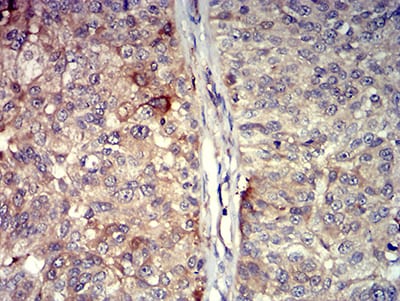

Immunohistochemical analysis of paraffin-embedded human bladder cancer tissues using TNFSF11 mouse mAb with DAB staining.

,